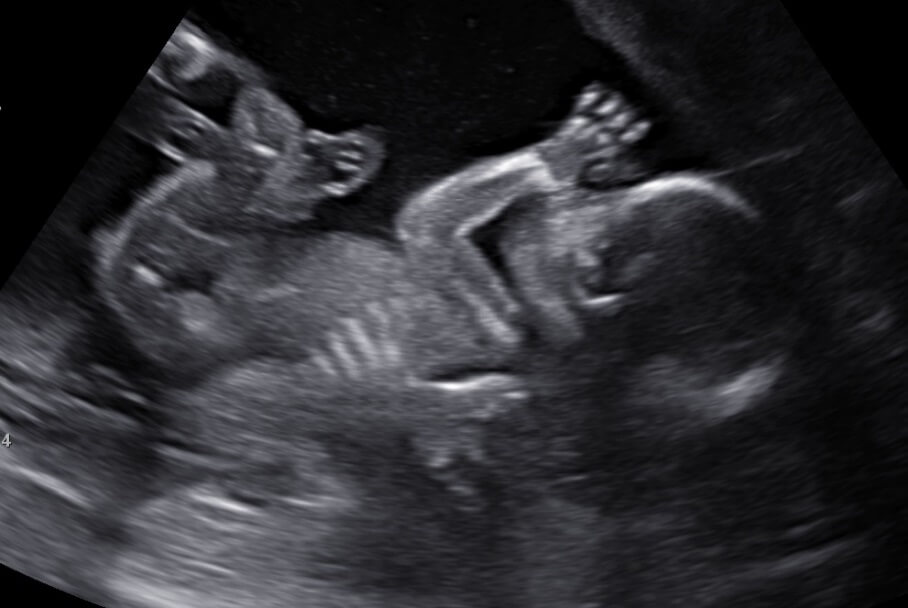

NIEUW: De 13 weken echo

Per 1 september 2021 is het voor zwangeren mogelijk een extra echo te laten maken. De 13 wekenecho is een medisch onderzoek. De echoscopist kijkt of er lichamelijke afwijkingen bij jullie baby te zien zijn. De 13 wekenecho lijkt veel op de 20 wekenecho. Natuurlijk kun...